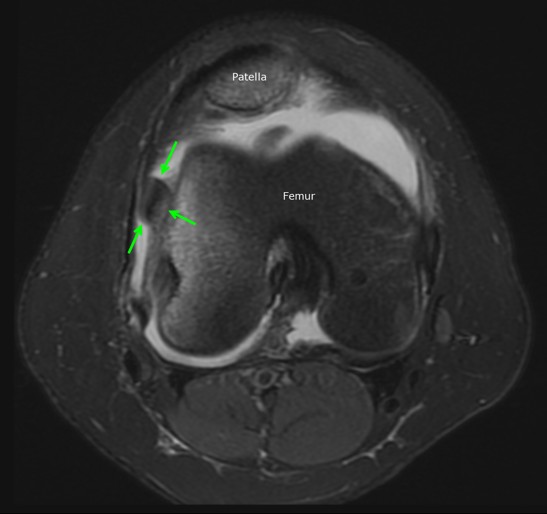

The diagnosis is typically made by history and physical examination. Knee x-rays are obtained initially to look for bone injuries, but cannot fully show the extent of soft tissue damage. For this reason, an MRI is performed soon after to assess the ligaments and cartilage and help determine whether surgery will be necessary. The MRI will also show underlying anatomical features that may predispose to the instability of the patella. If there is a significant injury to the cartilage covering the bone, a loose fragment in the joint, or tearing of the main ligament that stabilizes the patella, surgical treatment is recommended.

Luckily for Patrick Mahomes, the MRI did not show damage to the cartilage or ligaments. He was treated medically with physical therapy and able to return to play in a couple of weeks. The child with the MRI below was not as fortunate and required surgery to repair the patella. After a patellar dislocation, there is an increased risk of a recurrent dislocation, so continued follow-up and therapy are necessary.